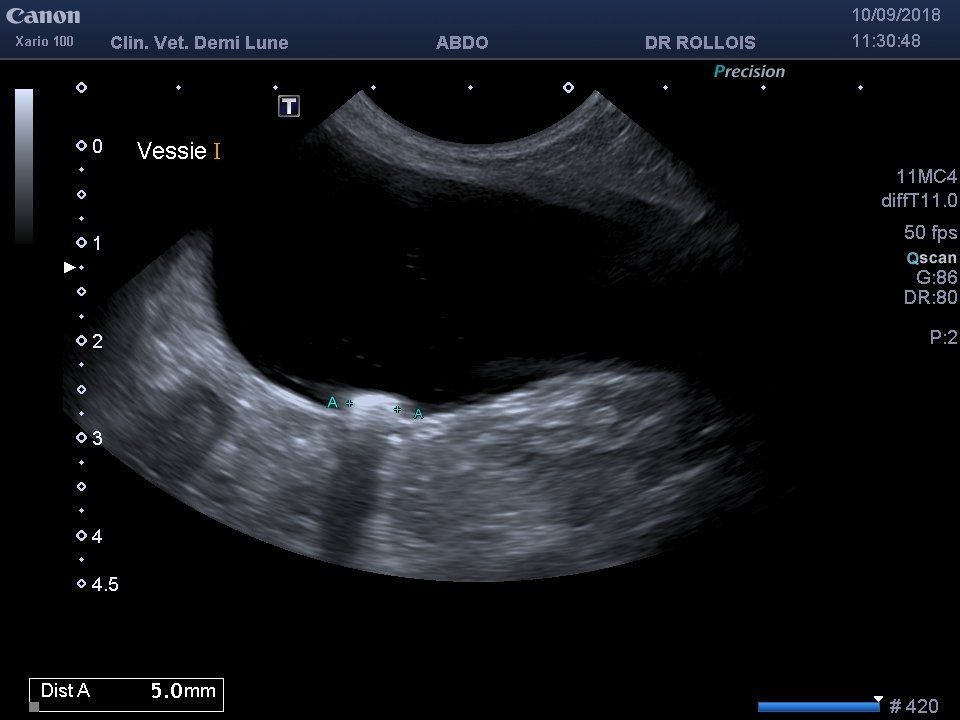

Le principe de l’échographie est d’envoyer des ultrasons qui sont plus ou moins réfléchis par les organes traversés. La sonde qui envoie les ultrasons les réceptionne et construit une image en fonction de leur intensité.

Cet examen est réalisé le plus souvent en votre présence et permet d’examiner les organes abdominaux (échographie abdominale), ou le cœur en activité (échocardiographie). L’échographe de la clinique vétérinaire demi-lune est récent et possède 3 sondes : une sonde pour l’examen des organes abdominaux et 2 sondes spécialisées dans l’examen cardiaque.

L’échographie abdominale est indiquée pour l’exploration des maladies des reins, de la rate, du foie mais aussi pour les diagnostics de gestation (visualisation des fœtus et des battements cardiaques), pour l’exploration du tube digestif et de certaines maladies hormonales.

En cas d’anomalie, certains prélèvements peuvent aussi être réalisés sous échographie : prélèvement urinaire (cystocentèse), prélèvements à l’aiguille fine, biopsies…

Les urines sont récoltées après prélèvement direct par vos soins, par sondage ou par cystocentèse (piqûre très peu douloureuse à travers la peau du ventre dans la vessie) guidée par échographie. Les analyses urinaires sont réalisées immédiatement dans le laboratoire de la clinique vétérinaire demi-lune.